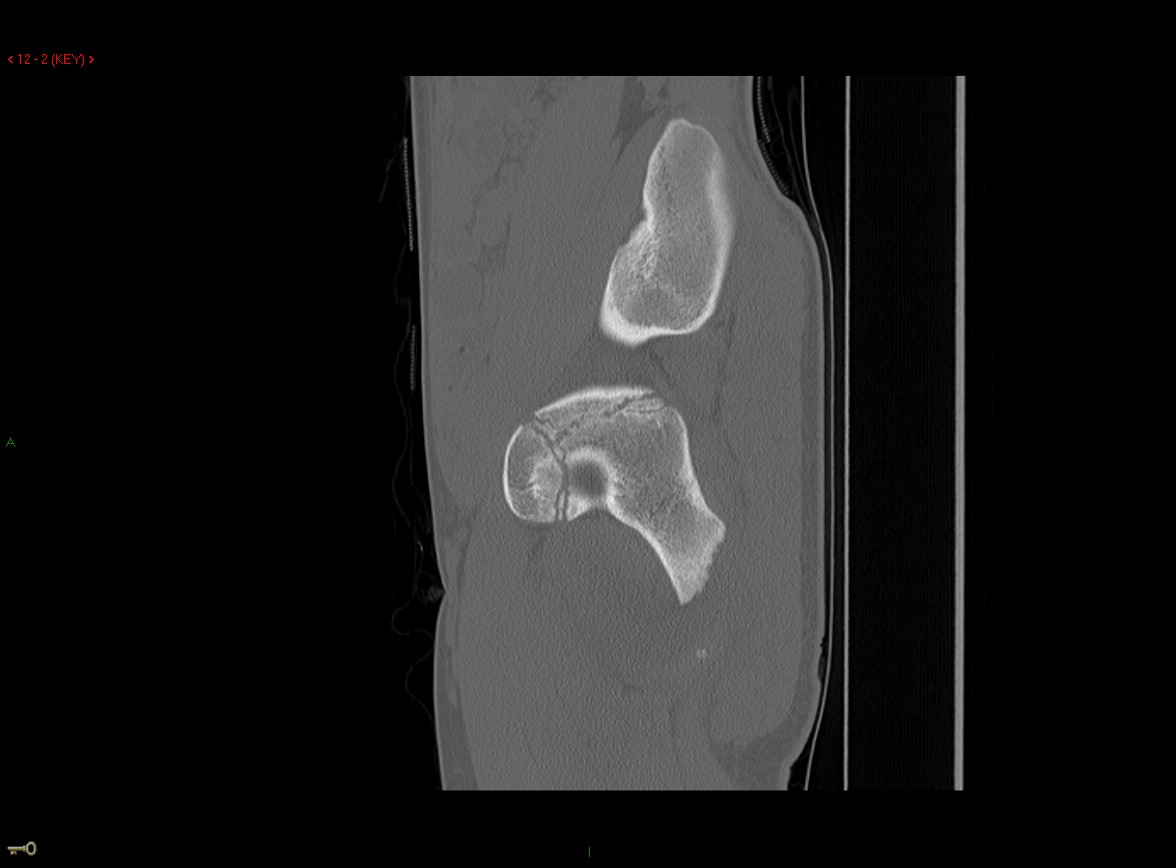

Figure 1 for case Ischial tuberosity ( RID2550 ) avulsion

Figure 1